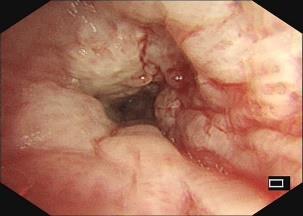

• 获得性免疫缺陷综合征合并马尔尼菲篮状菌导致肠道感染的内镜下表现(附6例报告)

2026, 32(3):84-88. DOI: 10.12235/E20250461

摘要 (32) HTML (27) PDF 3.50 M (26) 评论 (0) 收藏

摘要:目的 探讨获得性免疫缺陷综合征(AIDS)合并马尔尼菲篮状菌(TM)感染导致肠道感染的内镜下特征。方法 回顾性分析2022年11月-2024年10月于该院确诊为AIDS合并TM感染导致肠道感染的6例患者的临床资料。包括:临床症状、实验室检查、影像学检查、内镜检查和病理检查等。结果 6例患者中,男5例,女1例;发病年龄26~67岁;AIDS合并TM感染导致肠道感染患者的临床表现为:腹泻、腹痛、腹胀和恶心呕吐。其中,2例有消化道出血表现。实验室检查:6例患者外周血白细胞计数为(1.37~4.49)×109/L,血红蛋白计数为(67~99)g/L;CD4+T淋巴细胞为(1~52)个/μL,CD8+ T淋巴细胞为(61~321)个/μL,CD4+T淋巴细胞/CD8+T淋巴细胞比值为(0.01~0.18)。6例患者均行HIV RNA检测。其中,5例HIV RNA阳性。血培养:可见丝状真菌,报告显示为TM。影像学检查:6例患者CT结果可见肠系膜及腹膜后多发淋巴结肿大。内镜检查:6例患者内镜下均可见肠道病变。其中,十二指肠糜烂溃疡2例,结肠多发糜烂溃疡4例。病理检查:6例患者幽门螺杆菌(Hp)结果均为阴性,黏膜下可见成簇的小球形真菌孢子,符合TM感染;特殊染色:PAS(+),六胺银染色(+)。结论 当AIDS晚期患者出现消化道症状时,应警惕TM感染,病变部位常见于全结肠和直肠,亦可累及十二指肠,内镜下表现多为溃疡、糜烂和隆起性病变,形态表现无特异性;及时行胃肠镜检查、病理活检、特殊染色和免疫组化是确诊的关键。